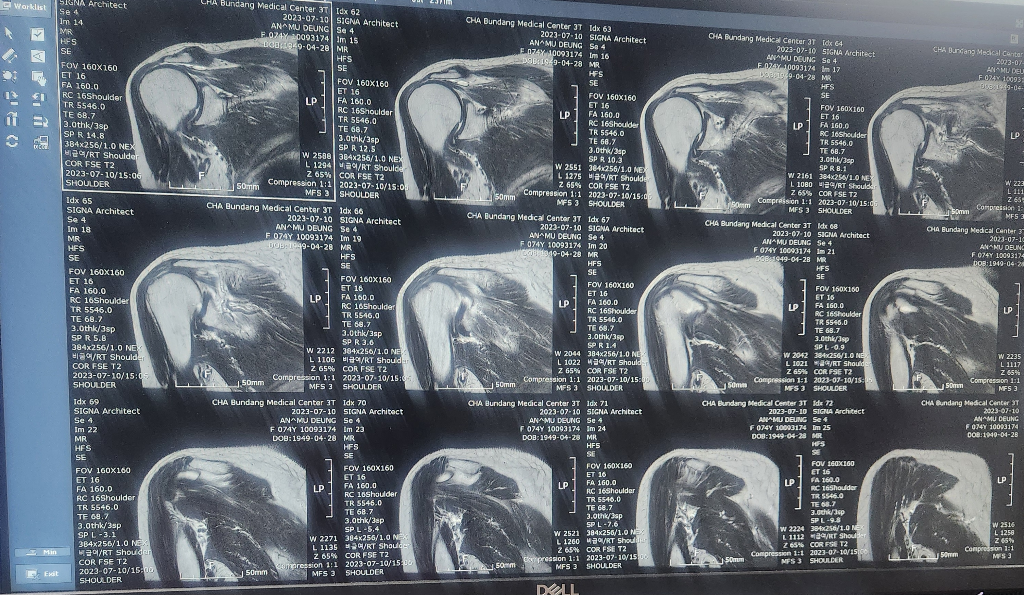

할머니가 넘어지면서 어깨를 다쳤는데

검사만하고 설명은 다음으로 미뤄져서요..

혹시 이 영상만으로 현재 어깨상태 문의드려도될까요

• 1번 째 사진

현재 어깨관절에 물이 차있는 소견으로 염증이 있는 것으로 보이며, 회전근개의 경우는 영상의 크기가 작아 정확한 판단은 어렵겠습니다.